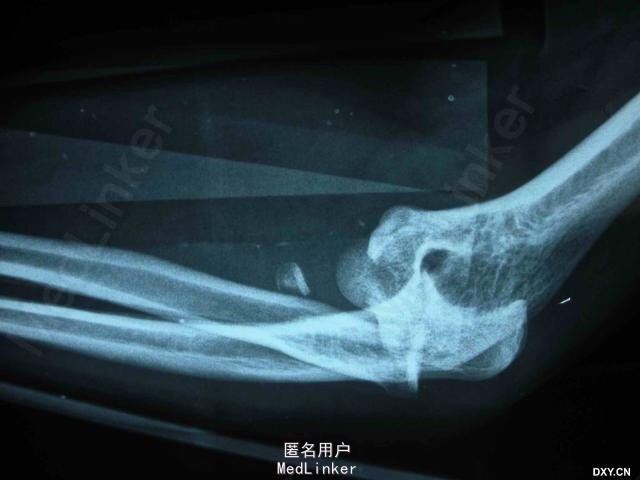

手法复位后X片及术后正侧位 初步诊断:左肘关节损伤三联征。治疗过程:尺骨冠状突骨折块复位固定、桡骨小头骨折块复位固定、内外侧副韧带修复、可活动式外固定支架固定。